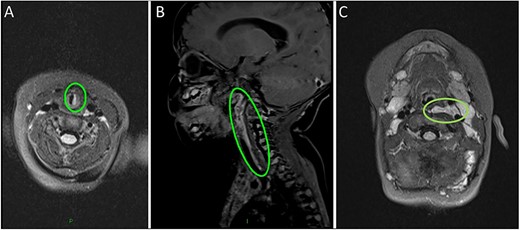

(A) MRI scan highlighting the subglottic infantile haemangioma. (B–C) Sagittal and axial MRI images of the carotid sheath haemangioma.

Magnetic resonance imaging (MRI) head/neck took place due to the presence of a facial plaque haemangioma (increased risk of PHACE syndrome) revealing an incidental lobulated lesion within the deep soft tissues of the left neck, measuring 2.7 × 7.4 cm with hyper-intense signal from the left carotid sheath (Fig. 2). The lesion extended from the skull base superiorly to the mediastinum inferiorly involving the left carotid space. The lesion extended between the internal and external carotid arteries. There was associated mass effect with effacement of the left pharyngeal mucosal space and left posterior oropharynx.